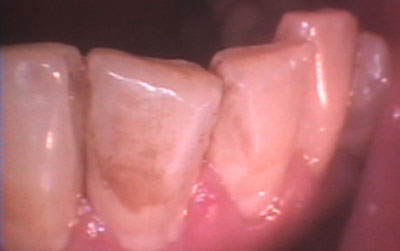

2. ΠΑΘΗΣΕΙΣ ΠΕΡΙΟΔΟΝΤΙΟΥ

Πέρα από τα δόντια, παθήσεις μπορεί να εμφανιστούν και στους ιστούς που στηρίζουν και περιβάλλουν τα δόντια (περιοδοντικοί ιστοί). Στην οδοντιατρική, οι νόσοι και οι βλάβες του περιοδοντίου (ουλίτιδα-περιοδοντίτιδα) αποτελούν τις πιο διαδεδομένες κύριες χρόνιες μη μεταδοτικές ασθένειες που αλληλοεπιδρούν και με σειρά από συστηματικές νόσους που μπορεί να έχει ο ασθενής (σακχαρώδη διαβήτη, ρευματοειδή αρθρίτιδα, καρδιακά νοσήματα, αιματολογικές διαταραχές, νόσοι του μεταβολισμού κ.ά.).

Οι περισσότεροι από εμάς χρειάζονται περιοδοντολογική φροντίδα, δηλαδή πρόληψη και θεραπεία νόσων – λοιμώξεων που προέρχονται από μικροοργανισμούς που στην πλειονότητα των περιπτώσεων βρίσκονται στο στόμα μας.

Περιστατικά που αντιμετωπίζονται στο ιατρείο μας

Στο ιατρείο ακολουθείται το νεότερο και πλέον σύγχρονο πρωτόκολλο θεραπείας (GBTguidedbiofilmtherapy), σύμφωνα με το οποίο ο οδοντιατρικός καθαρισμός, η θεραπεία ουλίτιδας και η περιοδοντική θεραπεία στη φάση ελέγχου της φλεγμονής και διατήρησης του αποτελέσματός της, πραγματοποιούνται με το πιο αποτελεσματικό, ήπιο και ελάχιστα επεμβατικό τρόπο.